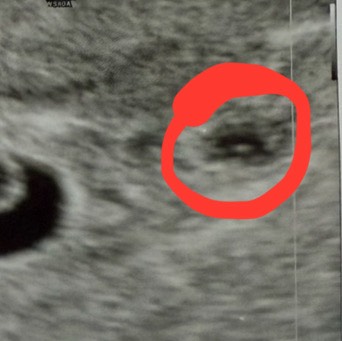

На узи рядом с эмбрионом нашли какую-то чёрную штуку, не объяснили что это, выглядит так же как и плодное яйцо, четко визуализируется, внутри без эмбриона, у кого такое было, кто знает, что это. На учет только 25.11

У знакомой гематома небольшая выглядела тоже к пя, может просто к другому узисту ещё сходить? . П не исключено что это второе плодное яйцо пустое, которое уже начало рассасываться ?